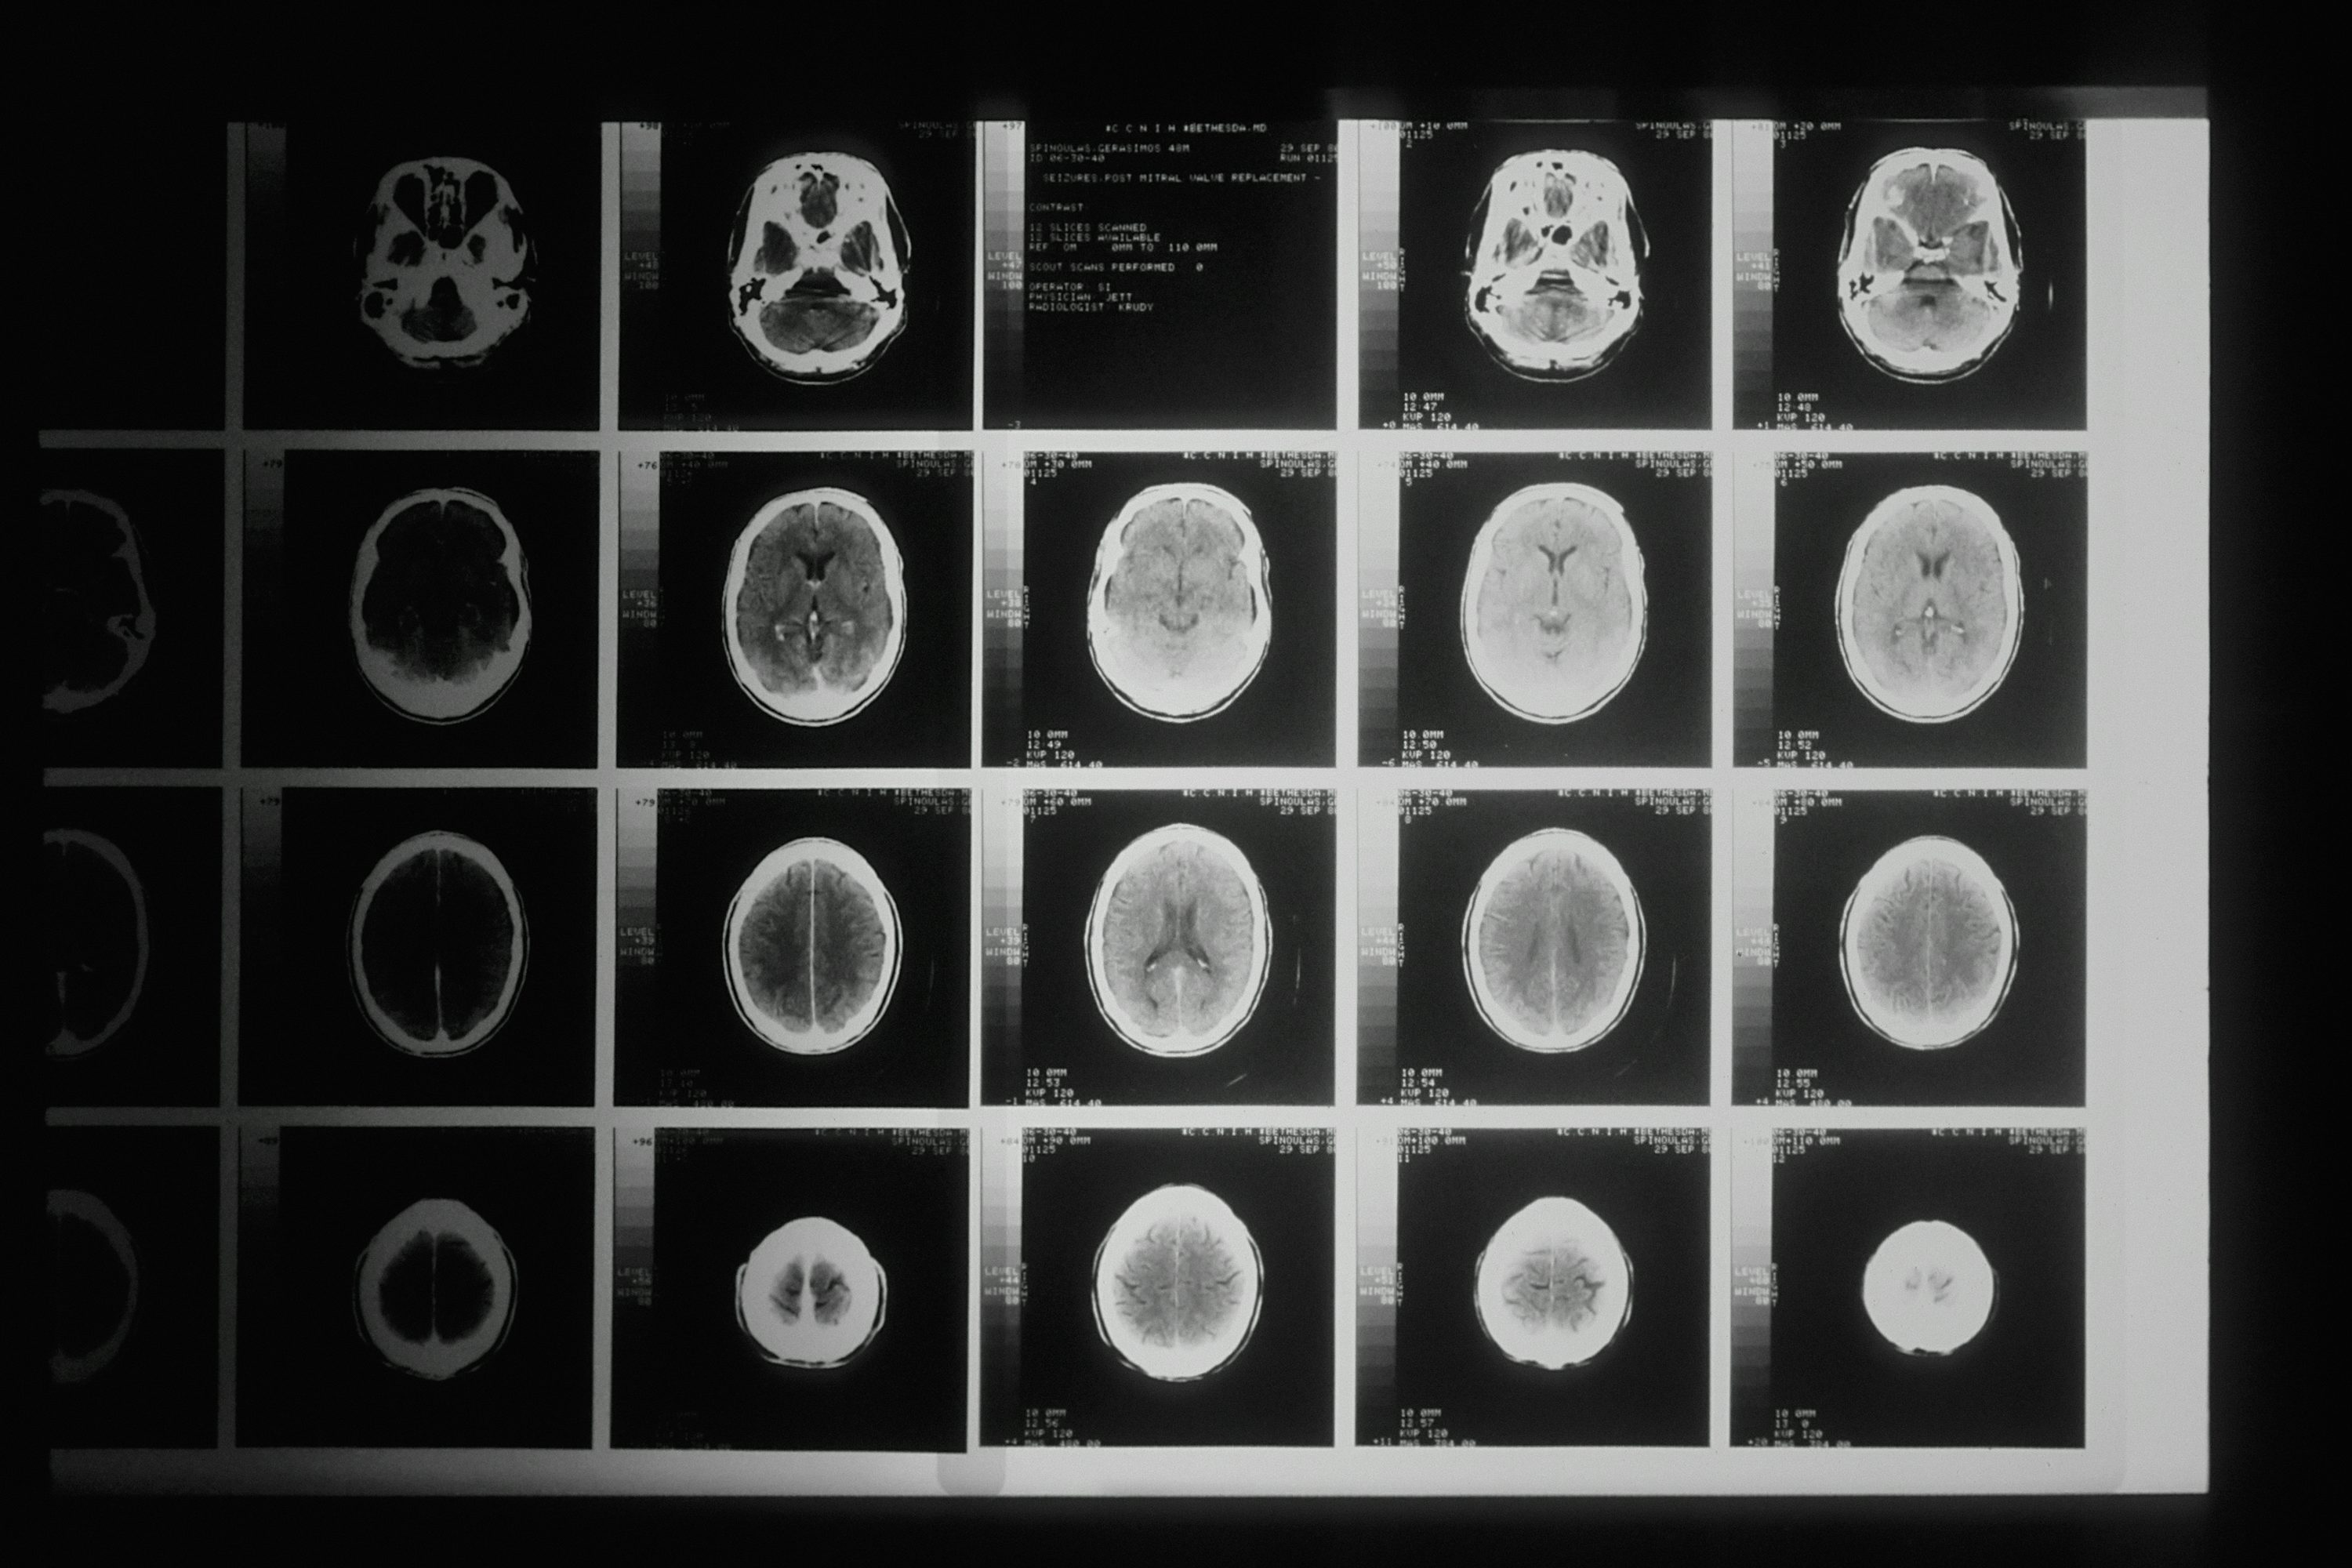

뇌동맥류는 MRI나 CT 혈관조영술로 조기 발견이 가능합니다. 5mm 이상의 동맥류가 발견되면 파열 위험이 높아 예방적 치료를 고려해야 합니다. 코일 색전술이나 클리핑 수술로 파열을 예방할 수 있으며, 40대 이상이거나 위험 요인이 있다면 뇌혈관 검사를 받는 것이 좋습니다. 금연과 혈압 관리는 동맥류 파열 예방에 필수적입니다.

정기적인 건강검진과 뇌혈관 검사로 조기에 위험 요인을 발견하는 것이 중요합니다. 40대 이상이거나 가족력이 있다면 혈압 측정과 함께 MRI 혈관조영술 검사를 받아보는 것이 좋습니다. 뇌동맥류나 혈관 기형이 발견되더라도 조기에 발견하면 예방적 치료로 출혈을 막을 수 있습니다. 복용 중인 약물이 있다면 정기적인 모니터링도 필수입니다.